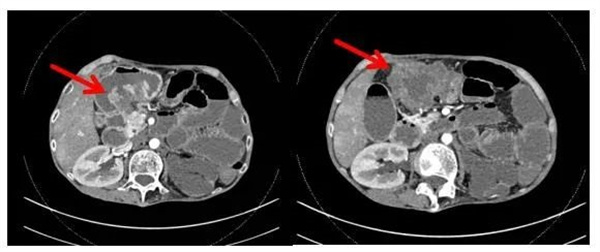

入院后,普通外科主任陈剑辉教授详细询问患者病史,同时完善相关检查,全腹CT显示横结肠占位性病变,考虑横结肠癌可能,并累及胃窦部、第2组小肠及结肠肝曲,其中部分与胃窦部相通,周围还伴淋巴结肿大及局部腹膜炎形成,有继发肠梗阻的迹象。

▲胃镜:胃体、结肠窦道形成(结肠Ca并胃肠瘘)